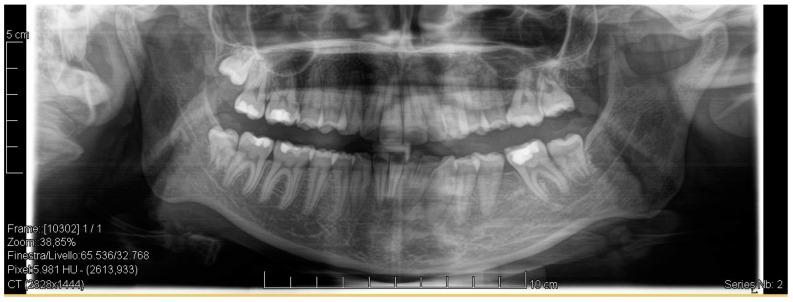

Successful closure of edentulous spaces with clear aligners (CAs) is influenced by many factors. CAs are tailored orthodontic devices whose predictability may have relevant medico-legal implications. This study presents a scoping review about missing molar space closure (MMSC) with CAs and a clinical case. This study aims to highlight the feasibility of molar space closure by mesialization with CAs without hybrid supports. Following PRISMA Sc-review guidelines, English-written randomized/non-randomized/observational clinical studies on PubMed, Scopus, Cochrane and Lilacs were searched. An 18-year-old patient, with upper and lower edentulous spaces due to the loss of two first molars, was rehabilitated with CAs (Sorridi, Sorridi srl, Latina, Italy) without hybrid supports and attachments. The therapy was carried out over 10 months. Currently, there are no studies documenting MMSC by mesialization with only CAs. Existing articles document the closure of premolar or incisor spaces. The upper and lower left second molars replaced the missing first molars, and erupting third molars replaced adjacent teeth. The biomechanical effects in space closure with CAs related to extraction cases appear as priorities of clinical/medico-legal interest. Our case turns attention to this movement of CAs without attachments/hybrid supports, indicating that even such a complex treatment can be comfortable for patients and safely predictable for specialists.

使用透明矫治器(CA)成功关闭无牙间隙受多种因素影响。CA是定制的正畸装置,其可预测性可能具有相关的医疗法律意义。本研究呈现了一项关于使用CA关闭缺失磨牙间隙(MMSC)的范围综述及一个临床病例。本研究旨在强调在无混合支持的情况下通过CA近中移动关闭磨牙间隙的可行性。遵循PRISMA范围综述指南,检索了PubMed、Scopus、Cochrane和Lilacs上英文撰写的随机/非随机/观察性临床研究。一名18岁患者因两颗第一磨牙缺失导致上下无牙间隙,使用CA(Sorridi,Sorridi srl,拉蒂纳,意大利)进行修复,无混合支持和附件。治疗持续了10个月。目前,尚无研究记录仅通过CA近中移动关闭MMSC的情况。现有文章记录了前磨牙或切牙间隙的关闭。上下颌左侧第二磨牙替代了缺失的第一磨牙,萌出的第三磨牙替代了相邻牙齿。与拔牙病例相关的CA关闭间隙的生物力学效应似乎是临床/医疗法律关注的重点。我们的病例将注意力转向了无附件/混合支持的CA这种移动方式,表明即使是如此复杂的治疗对患者来说也可以是舒适的,对专家来说也可以是安全可预测的。